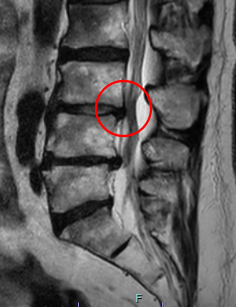

治療前

┃検査・診断

腰椎MRIを確認したところ、赤い枠内のL3/4で脊柱管が狭窄しているのを確認しました。そのため痛みの原因はL3/4部分の「脊柱管狭窄症」だと診断しました。